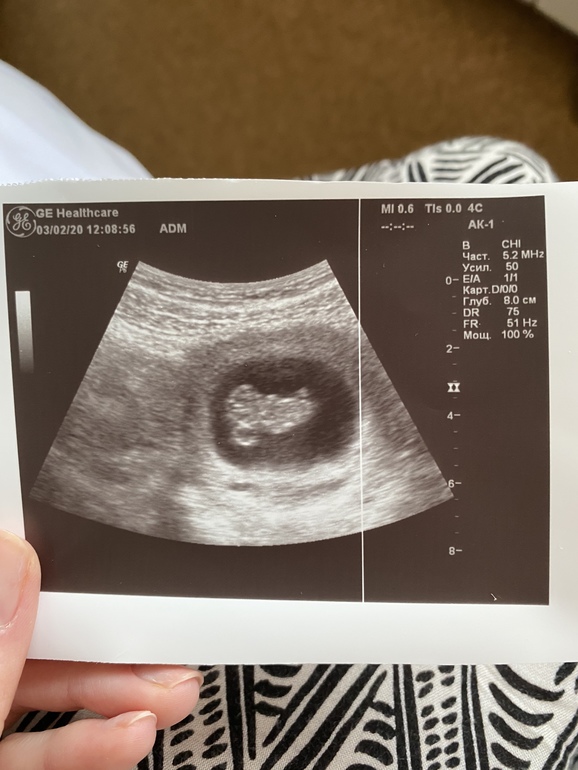

Узистка очень умилилась положению моей пчелки, и сказала, что с желточным мешочком похожа на ангелочка (фото прилагаю). 🥰